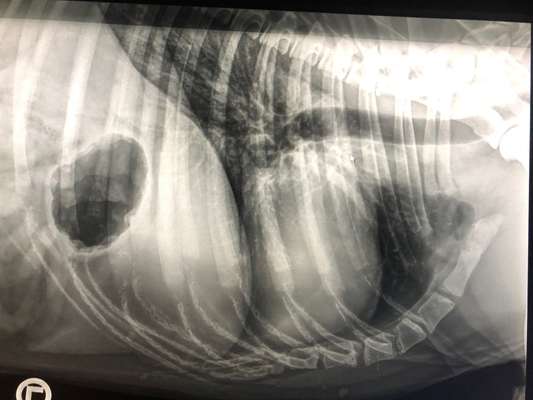

Hallo mein Hund Jack hatte heute eine Voruntersuchung mit Röntgen Ich würde sie bitten vielleicht mal ein Auge mit drauf zu werfen und mich ein bisschen zum Fall aufzuklären die Ärzte meinte nur ein leicht vergrößertes Herz und die Lunge schaut nicht gut aus aber mehr sagten sie mir nicht jetzt mache ich mir natürlich dauerhaft sorgen jetzt und frage was ich noch machen könnte Info Zu Jack Dobermann 4jahre Aus Rumänien Bei mir in 2ter hand Und so immer fröhlich und fit drauf

Das Röntgenbild allein sagt also leider noch nicht viel über die Herzgesundheit deines Hundes aus. Die Lunge auf dem Bild ist leider schlecht zu beurteilen. Die Röntgenaufnahme wurde vermutlich im Zustand der Exspiration (Ausatmung) getätigt. Um eine Lunge sachgerecht auf einem Röntgenbild beurteilen zu können, sollte das Bild im Zustand der Inspiration (Einatmen) geschosssen werden. Zeigt dein Hund denn Atemprobleme? Hustet er gelegentlich? Oder ist er schnell außer Atem?